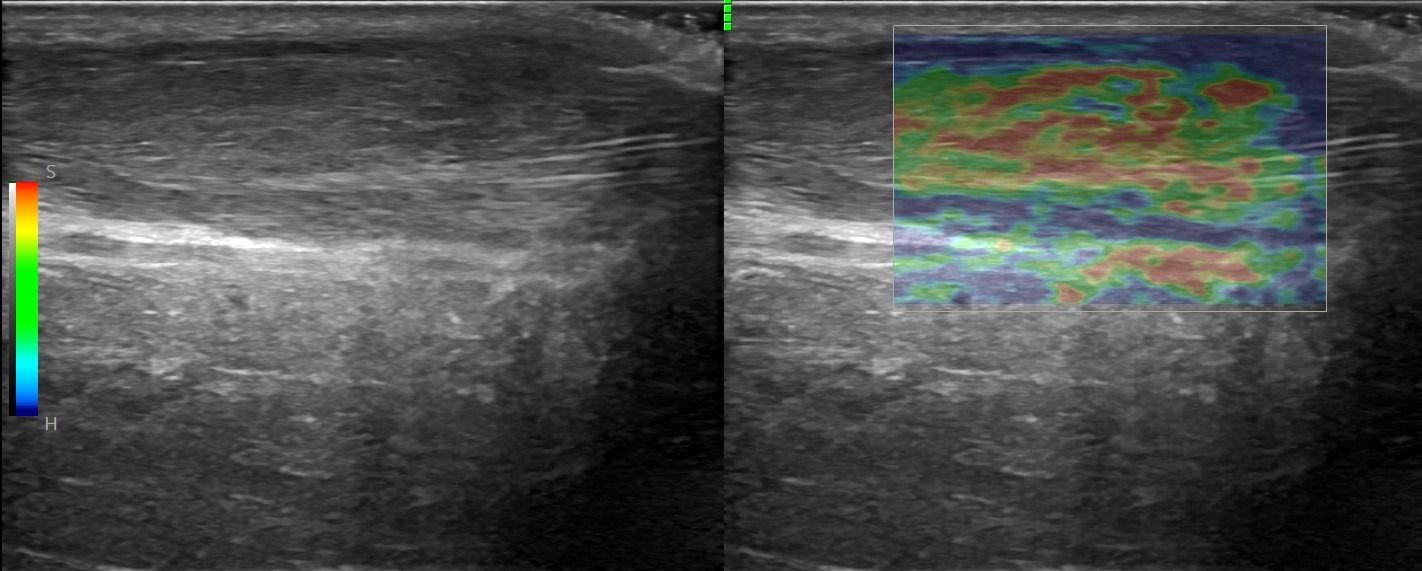

Foot Tendons

Foot Ultrasound allows the diagnosis of tendonitis, tenosynovitis, and rupture in the following tendons:

- Achilles Tendon

Dynamic Testing: The dynamic nature of ultrasound allows for the assessment of the foot during movement. This possibility is particularly useful for evaluating pathologies affecting the range of motion of the foot.